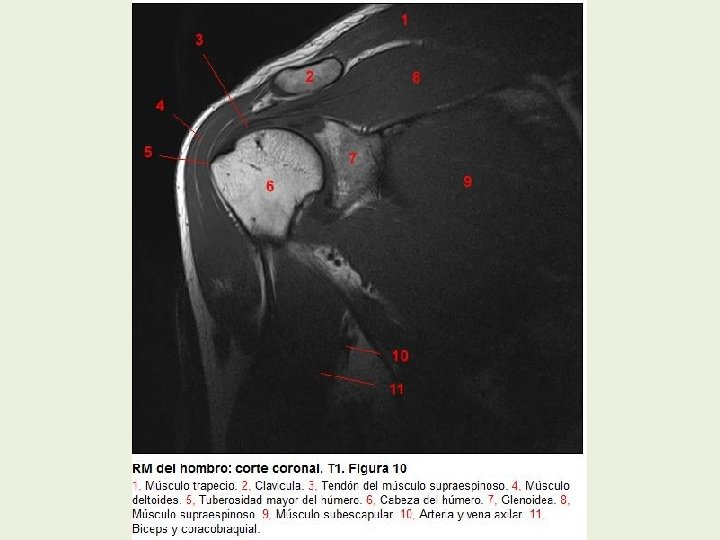

Hombro Cortes coronales RMN